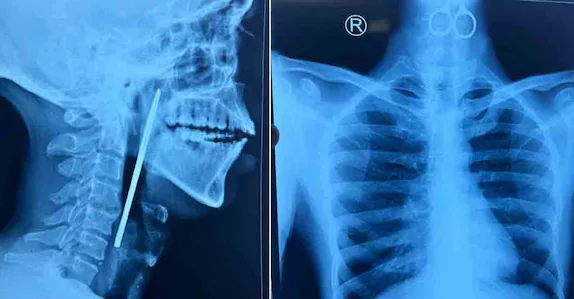

ഗവ. മാനസികാരോഗ്യ കേന്ദ്രത്തിലെ രോഗി കത്രിക വിഴുങ്ങി; അടിയന്തിര ശസ്ത്രക്രിയയിലൂടെ പുറത്തെടുത്തു

കോഴിക്കോട് ∙ ഗവ. മാനസികാരോഗ്യ കേന്ദ്രത്തിലെ രോഗി വിഴുങ്ങിയ കത്രിക ഗവ. മെഡിക്കൽ കോളജ് ആശുപത്രിയിൽ നടത്തിയ ശസ്ത്രക്രിയയിലൂടെ പുറത്തെടുത്തു. ഭക്ഷണം കഴിക്കാത്തതിനെ തുടർന്ന് തിങ്കളാഴ്ച വൈകിട്ടാണ് യുവാവിനെ അത്യാഹിത വിഭാഗത്തിൽ പ്രവേശിപ്പിച്ചത്. അന്നനാളത്തിൽ കത്രിക കുടുങ്ങി കിടക്കുന്നതായി എക്സറേ പരിശോധനയിൽ…